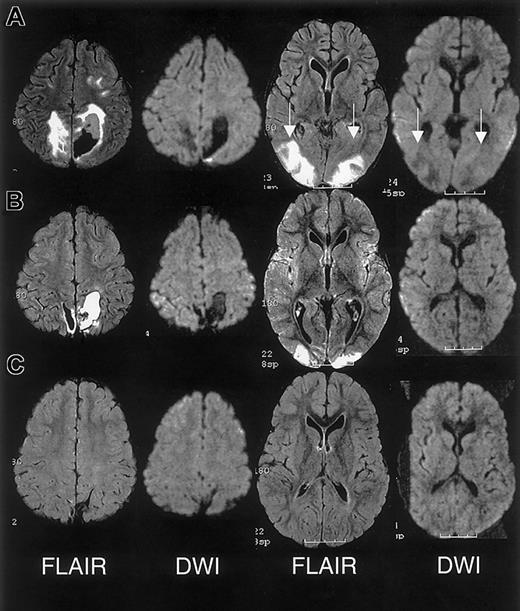

One year prior to ACS episode, the patient had normal MRI/MRA and transcranial Doppler studies. MRI on day 10 and 1 month following discharge revealed RPLS with superimposed ischemic white matter changes (Figure 2).

MRI findings for case 2.

Multifocal areas of signal hyperintensity predominantly limited to the cortex of the posterior parietal and occipital lobes on FLAIR T2-weighted images, including punctate areas of abnormality in the deep, periventricular white matter of the right frontal lobe and of the cortex of the right medial parietal lobe. MRI done 1 month following discharge revealed punctate lesions in the frontal lobe, representing subacute to chronic ischemic changes, but resolution of the T2 hyperintense lesions in the posterior distribution.